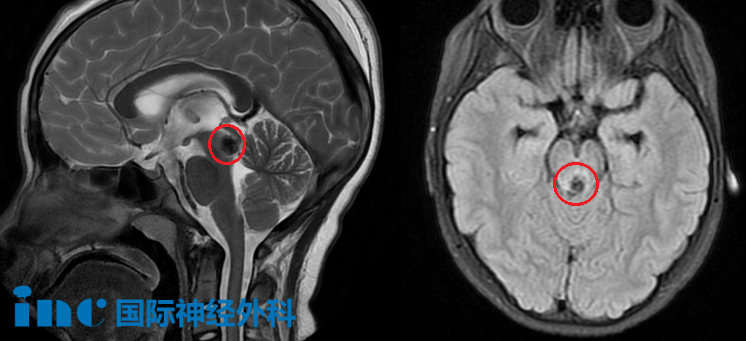

2021年,因为持续数日的头晕、乏力、睡眠质量下降呕吐,阿豪就医检查,本以为就是一次简单的小毛病。

但是却不想竟是“生命中枢”——脑干上出了问题。头部CT显示延髓后方近小脑见大小约6.8*9.9mm的片状高密度阴影,怀疑脑干海绵状血管瘤。

2023年3月29日,在国内手术团队的配合下,术中神经电生理监测下,巴教授全程主刀顺利全切了阿豪的脑干海绵状血管瘤。